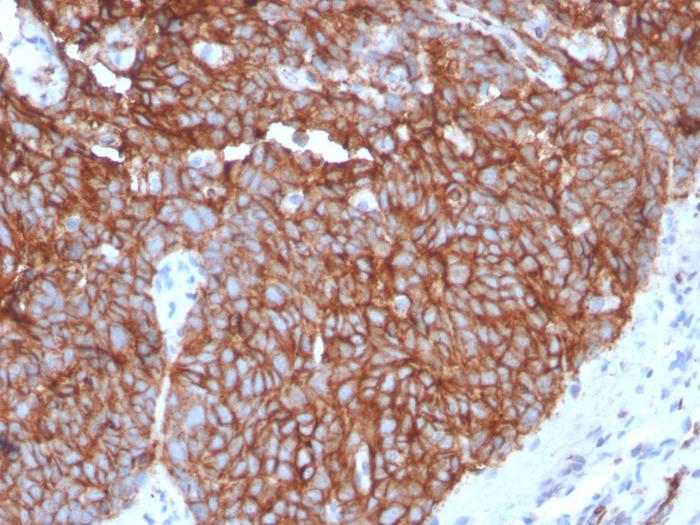

Recognizes a protein of 55 kDa, which is identified as GLUT-1. Glucose transporters are integral membrane glycoproteins involved in transporting glucose into most cells. There are many types of glucose transport carrier proteins, designated as Glut-1 to Glut-12. Glut-1 is a major glucose transporter in the mammalian blood-brain barrier. It is expressed in high density on the membranes of human erythrocytes and the brain capillaries that comprise the blood-brain barrier. Glut-1 is expressed at variable levels in many human tissues. Overexpression of Glut-1 has been linked to tumor progression or poor survival of patients with carcinomas of the colon, breast, cervical, lung, bladder and mesothelioma. Glut-1 is a sensitive and specific marker for the differentiation of malignant mesothelioma (positive) from reactive mesothelium (negative). Primary antibodies are available purified, or with a selection of fluorescent CF® Dyes and other labels. CF® Dyes offer exceptional brightness and photostability. Note: Conjugates of blue fluorescent dyes like CF®405S and CF®405M are not recommended for detecting low abundance targets, because blue dyes have lower fluorescence and can give higher non-specific background than other dye colors.

Positive Control

K562, A431, MDA-MB-231 cells. Erythrocytes. Mesothelioma or breast, colon and ovarian carcinoma.

Antibody target cellular localization

Plasma membrane

Tumor expression

Bladder cancer|Breast cancer|Cervical cancer|Gastrointestinal cancer|Lung cancer|Mesothelioma